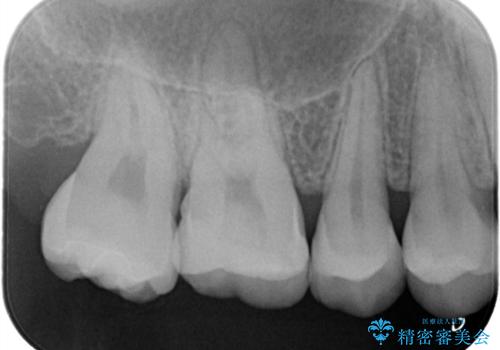

【セラミックインレー】咬合面のカリエス

- メンテナンス時に見つかった虫歯です。二次カリエスのリスクを下げる為に虫歯を除去後セラミックインレーで治療を行いました。

咬合面の溝が深く虫歯のリスクが大きい患者様です。

他の歯も咬合面に同じように虫歯ができて大きくなってしまった経験があることから今回は大きくそして深く進行する前に虫歯を除去しセラミックインレーで治療を行いました。